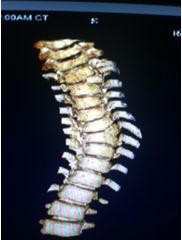

At age 10 Michael had to go to another new orthopedic specialist. His new surgeon had a very calm demeanor and really helped to put Michael’s anxiety at ease. He started having x-rays twice a year at age 11. By age 12 Michael had some symptoms of tethered spinal cord again and had a repeat surgery at age 12 ½. He had his first CT scan of his spine completed and it gave a little more details to his vertebral anomalies. It was very cool seeing his spine in 3D. Michael always had a great sense of humor through his scoliosis journey. He could not wait until 7th grade to do the scoliosis test in PE class. He of course, did not tell the visiting nurses that he already had a diagnosis because he wanted to see their faces when he bent over. He finally told them after they got the 3rd nurse go come over and look at him.